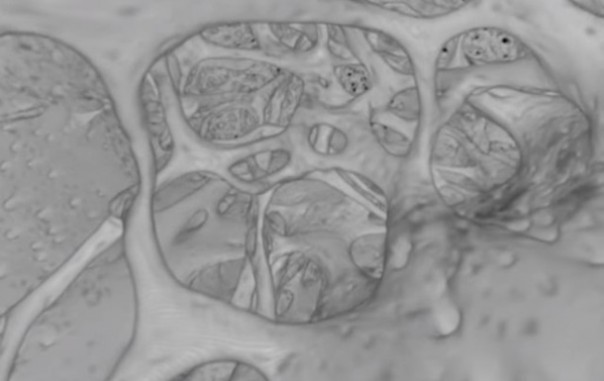

Научная группа провела несколько экспериментов на мышах. Специалисты выяснили, что GDF11 помогает имитировать действие диет, которые доказали свою эффективность в предотвращении болезней сердца и онкологических заболеваний. Кроме того, инъекции белка старым грызунам приводили к восстановлению кровеносных сосудов в мозге и усилению нейрогенеза.